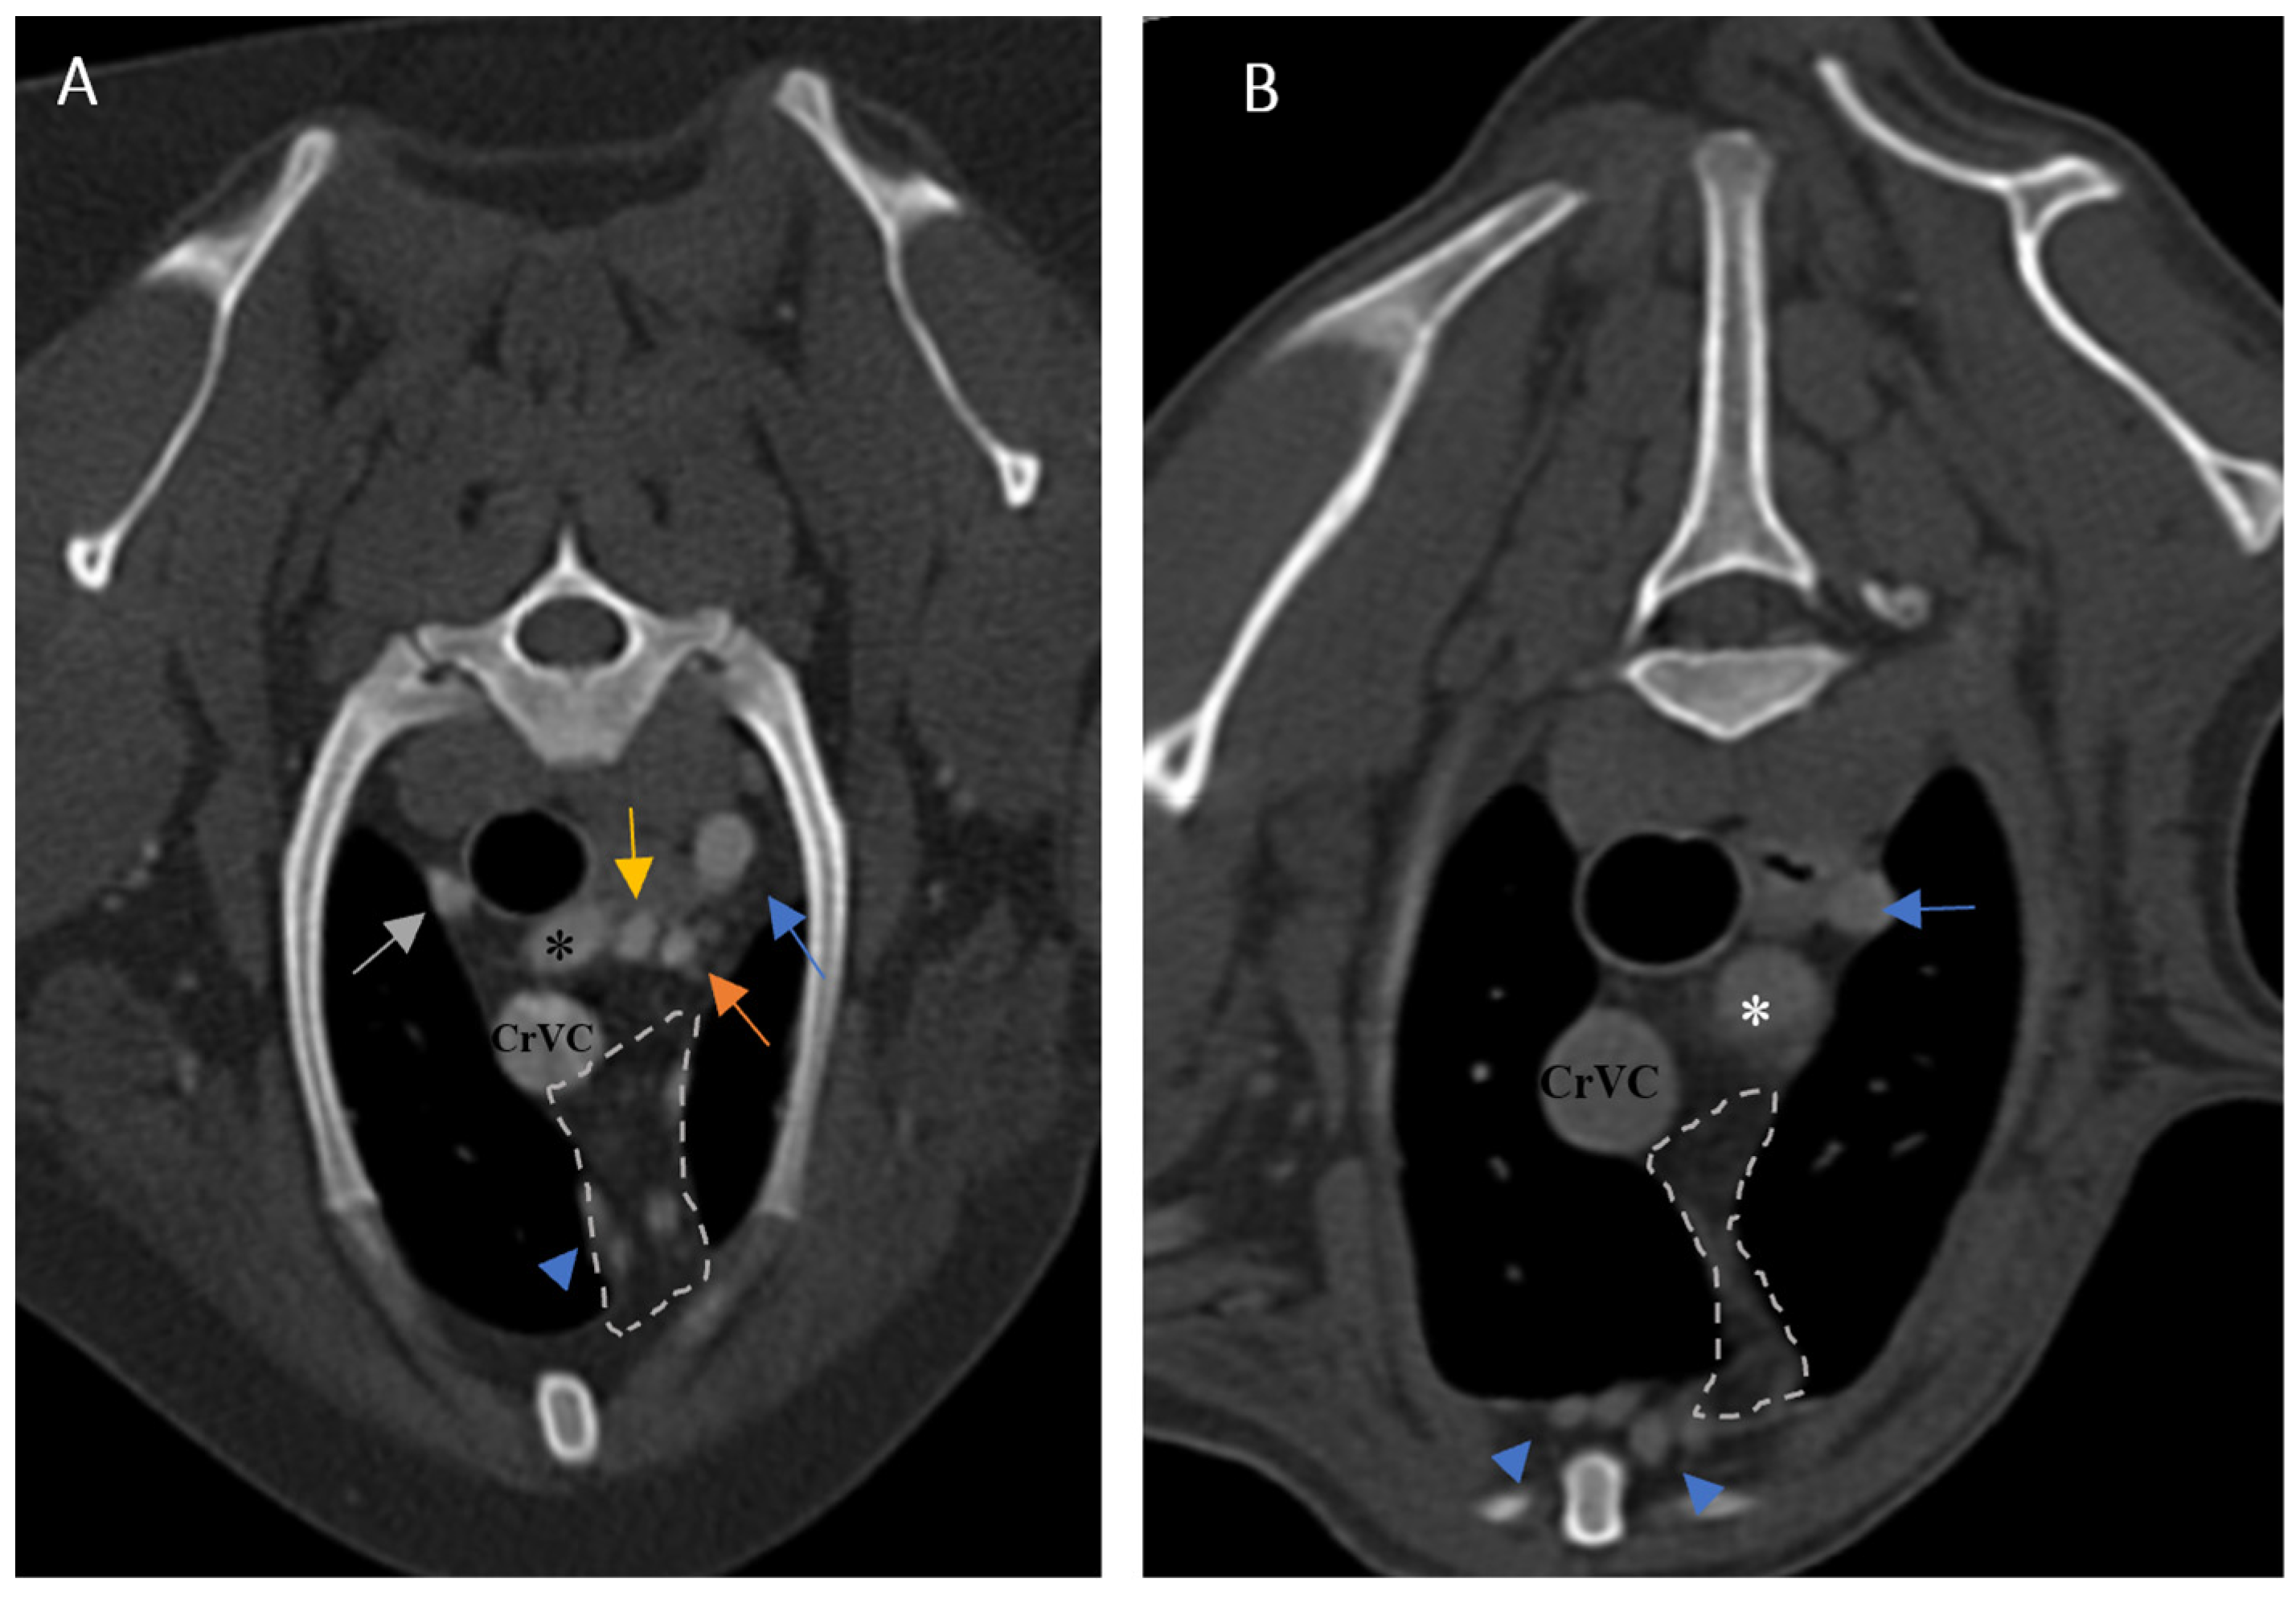

Figure 7. Illustration of non-visible grade 0 thymus and topographic location of thymus in contrast-enhanced transverse sections of the thoracic region CT scan examination at the level of T2. (A): Ten-year-old female mixed-breed dog. The thymus is grade 0 (non-visible), wedge shaped with homogenous appearance, left-sided predominancy and straight borders (CT number: −137). (B): One-year-old female mixed-breed dog. The thymus is grade 0 (non-visible) and wedge shaped with homogenous appearance, left sided-predominancy and concave borders (CT number: −156). CrVC: cranial vena cava, T: trachea, E: esophagus (which is dilated due to general anesthesia), grey arrows: degenerated thymus, blue arrows: left subclavian artery, yellow arrows: right common carotid, orange arrows: left common carotid artery, green arrows: internal thoracic artery, arrowhead: internal thoracic veins, and asterisks: right subclavian artery.